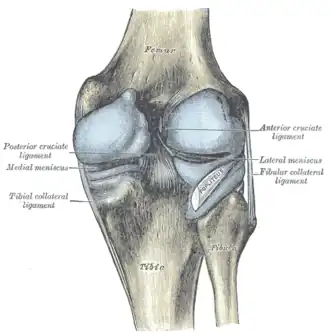

Right knee joint, from the front, showing interior ligaments

Right knee joint, from the front, showing interior ligaments -